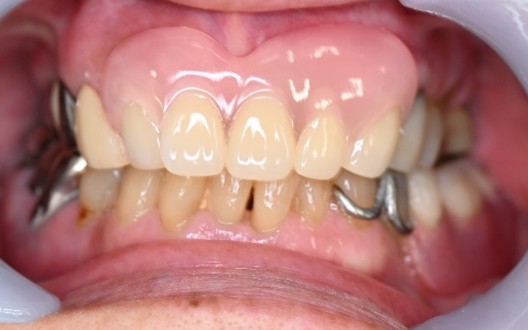

After

【義歯を装着したところ】